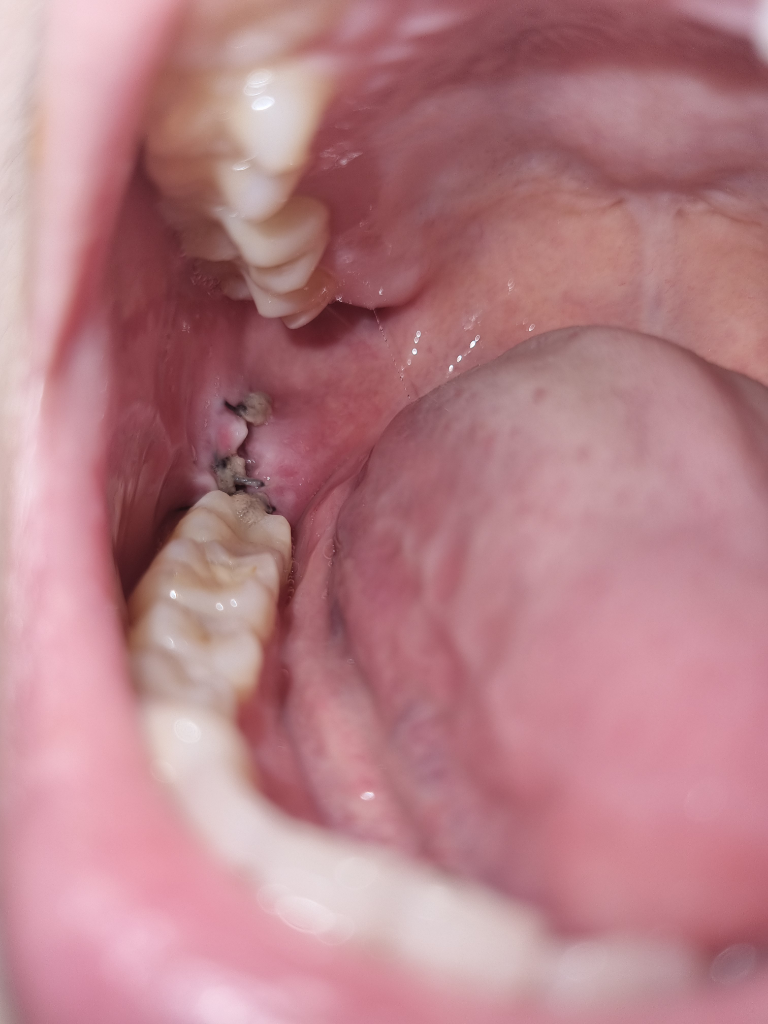

사랑니 발치후 ㅠㅜ 욱신거려서

사진 처럼 사랑니를 발치후 꼬맷는데 꼬맨게 풀렸는지 그 사이로 음식물이 들어갔어요 ㅠ 실을 빼고도 음식물 들어가고 잘 안빠지면 어쩌죠? 치과에서 선생님이 가글 같은거나 물 오물오물 하면 잘 빠진다던데 저상태에서 절대 안빠지고 지금 조금 욱신 거려요 ... 분명 빼고 바로 봤을때는 다 꼬매져있었는데 꽁꽁..

사진상으로는 그다지 문제가 보이진 않습니다. 물로 안빠지면 그냥 두시면 잇몸차오르면서 빠집니다.